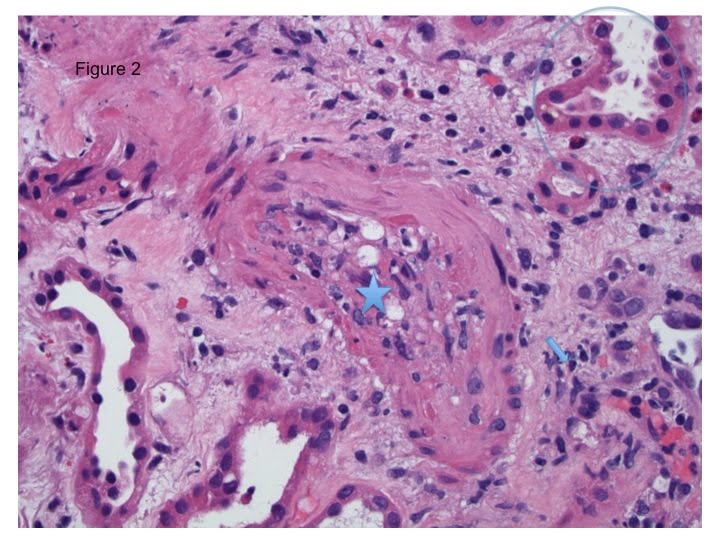

*Fibrinoid necrosis (seen as the red pink color, Figure 1, star) will automatically indicate Banff type 3 T cell mediated rejection TCMR or severe rejection. Compare the Fibrinoid necrosis of this arteriole to the normal arterial tissue seen in Figure 1 marked by the arrow. To review Banff classification review Nate’s prior post.